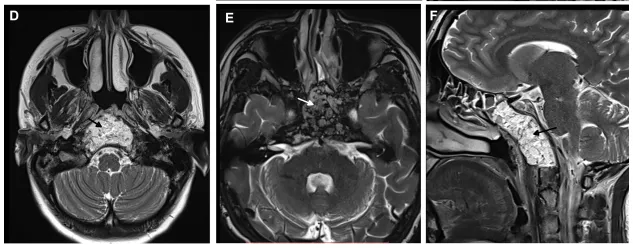

一名48岁的女性因右侧第六神经麻痹前来就诊。MRI显示一个大型斜坡脊索瘤,延伸至颞骨岩部、海绵窦、关节突和颈静脉孔、蝶筛隐窝以及咽后空间,疑似有硬脊膜内成分。

从蝶筛水平到蝶腭弓处,对右侧鼻中隔黏膜进行垂直切口,广泛开放蝶窦。进一步磨除斜坡骨质,暴露肿瘤下部。使用30°、45°和70°角度内镜以及弯曲和可塑型手术器械切除肿瘤。

术后MRI确认了肿瘤的完全切除。在2个月的随访中,内镜检查未发现结痂,患者也未抱怨有任何鼻部不适。

一名57岁的男性患者,因出现第Ⅵ对颅神经(外展神经)麻痹相关症状而前往医院就诊。经过检查,他的症状是由斜坡肿瘤引起。在当地,他接受了斜坡病变的活检手术,术后病理结果确认为脊索瘤。然而,在进行了活检手术后,该患者出现反复鼻出血,而当地医疗未能及时确定出血的原因,后转院至法国巴黎Lariboisiere大学医院向福教授寻求治疗。

该患者的磁共振成像(MRI)结果显示,他的病变位于斜坡的上部和中部,同时存在一个较大的鼻中隔穿孔,提示在之前的内镜活检过程可能已经损伤了鼻中隔动脉,从而导致他持续地鼻出血,极大地影响了日常生活质量。经过对患者的全面检查和评估,福教授认为应当进行肿瘤切除以及血管修复手术。

针对该患者的情况,福教授采取了一种改良手术入路策略——神经内镜扩大经鼻入路:通过右侧单鼻孔入路到达斜坡,切开蝶骨嘴黏膜,磨钻磨除蝶骨嘴和蝶窦(SS)下方的斜坡以到达肿瘤,并在重建结束时缝合黏膜切口(类型I)。

术后MRI显示肿瘤被完全切除,手术顺利。患者术后恢复顺利,期间没有鼻部不适。在2个月随访时,内镜检查显示鼻窦上方由术前的白色粘膜转变成健康的粉红色黏膜,恢复正常。

术后MRI影像明确肿瘤全切情况,以及用于重建的自体脂肪